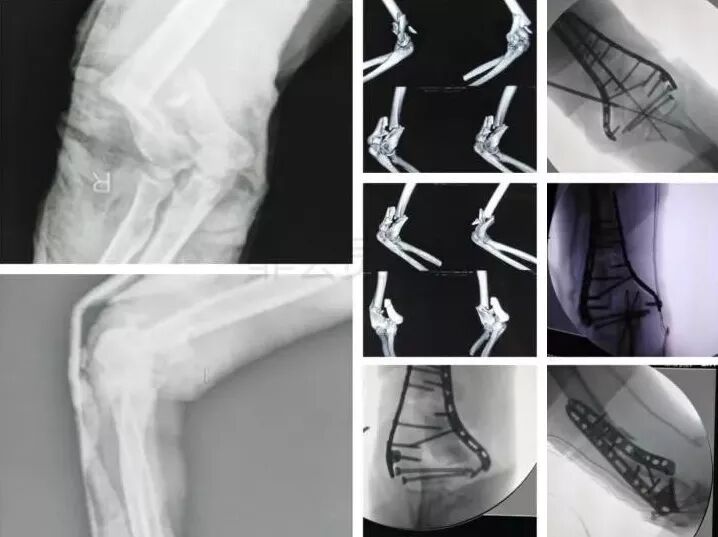

3)肱骨远端骨折

图片

• 骨筋膜室综合征,立即减压。

• 前臂三大神经,肘血管损伤均可以探查。

4)复杂肘关节骨折(尺骨鹰嘴,桡骨头)

• 伤后1周内手术

• 2周后手术-骨化性肌炎

• 术后尽量不要肘关节制动,制动不超过2周。